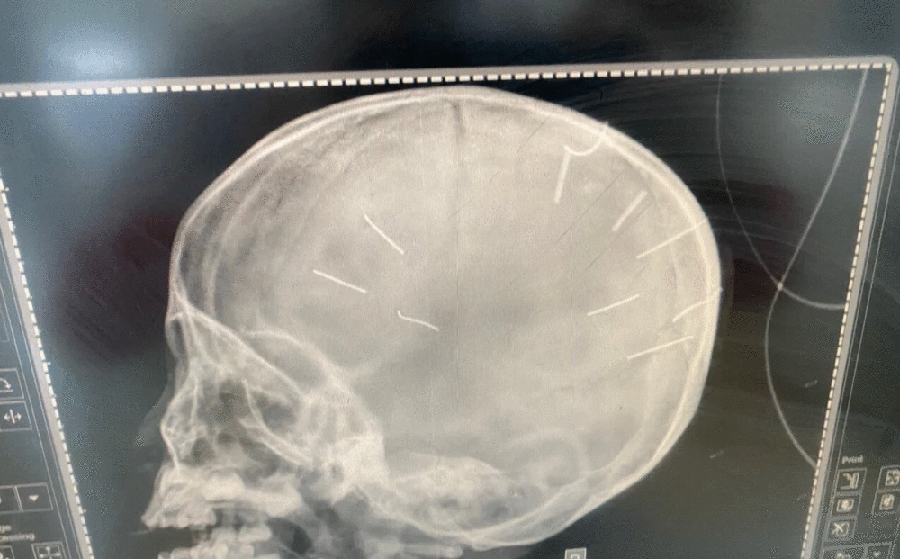

Từ lúc này, A ba lần phải nhập viện: Lần đầu xuất hiện dị vật ở mũi, điều trị tại Bệnh viện Nhi Trung ương điều trị. Lần thứ hai ngộ độc thuốc sâu phải đưa vào Bệnh viện Đa khoa huyện Thạch Thất, sau đó đưa lên Bệnh viện Nhi Trung ương. Lần thứ ba chỉ cách đây một tháng, phát hiện ba cây đinh nhỏ trong đường tiêu hóa...